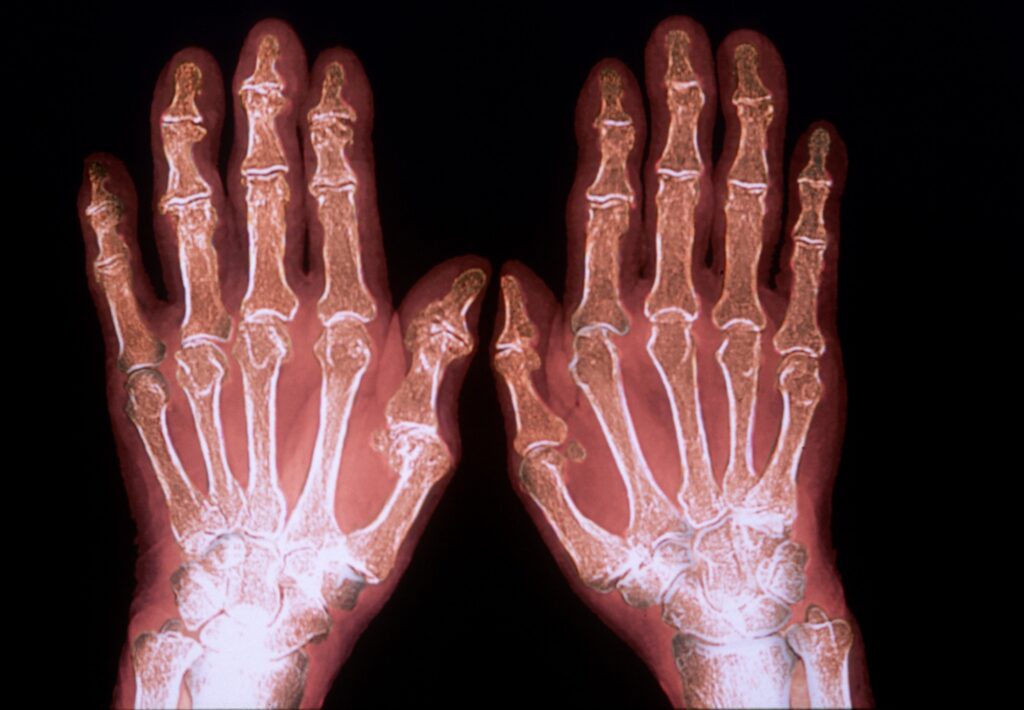

• Imaging tests like X-ray, Ultrasound, or MRI to assess joint inflammation and early damage